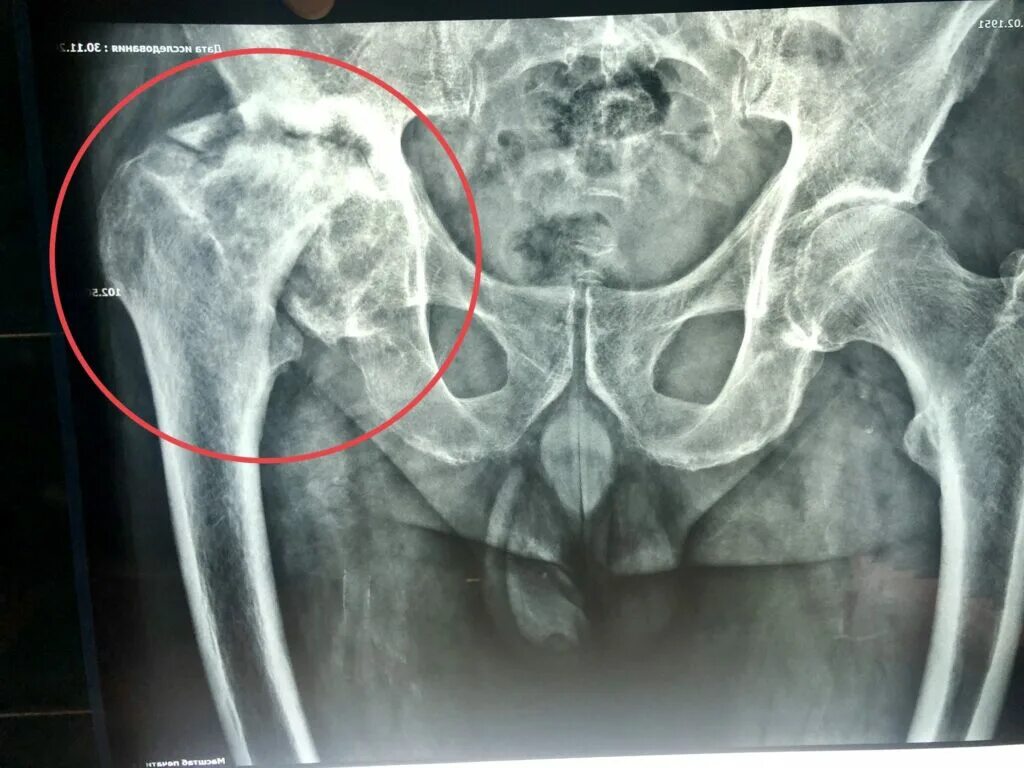

Инвалидность при некрозе тазобедренного сустава